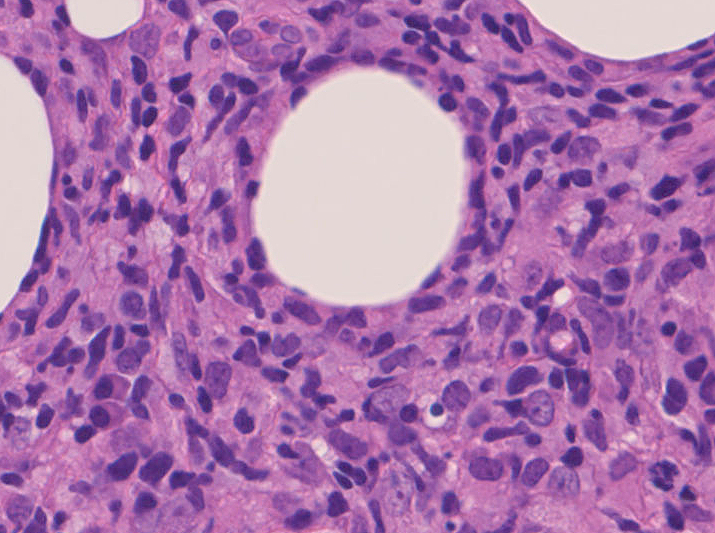

リンパ腫の定義: SPTCLは成熟細胞障害性T細胞(cytotoxic T-cell)由来で、皮下組織に脂肪識炎に似た組織像を呈しながら増殖する悪性リンパ腫。

皮下組織に優位な, 小~中型 Tリンパ球の密な浸潤が特徴。ときに大型リンパ球や組織球が混在する。 リンパ球の異型は, わずかなものから明瞭な異型を示す症例までさまざまである。